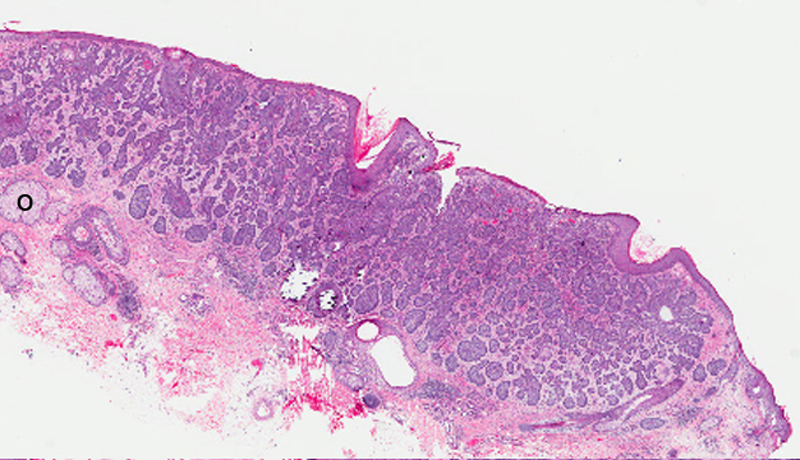

Basal cell carcinoma

Cords or Islands of basal cells with nuclear palisading of peripheral cell layer in the dermis. Retraction artifact may be seen as an empty space between the stroma and tumor island. Morpheaform (sclerosing type) shows islands and cords of flattened tumor cells in the dermis.